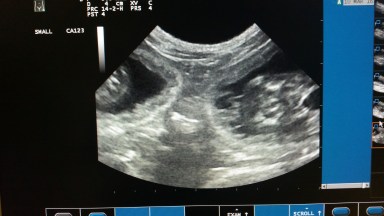

Donderdag 10 maart 2016: echo

Omdat Ushi vorig jaar al haar kittens verloor (drie bij de geboorte en een na een week) willen we nu zo min mogelijk risico’s lopen en zijn we vandaag naar de dierenarts geweest om een echo te laten maken om te zien of tot hier aan toe alles goed verloopt. Ushi gedroeg zich fantastisch en liet gewillig haar buikje scheren, de koude gel erop smeren en lag zelf mee naar de beelden te kijken. Na wat zoeken en goed rondkijken kwamen we met zijn alle tot de conclusie dat er twee mooie, zeer levendige, kittens zijn. Het viel dan ook niet mee om daar een goede foto van te maken, want ze waren zo weer “verdwenen” als ze goed in beeld waren.